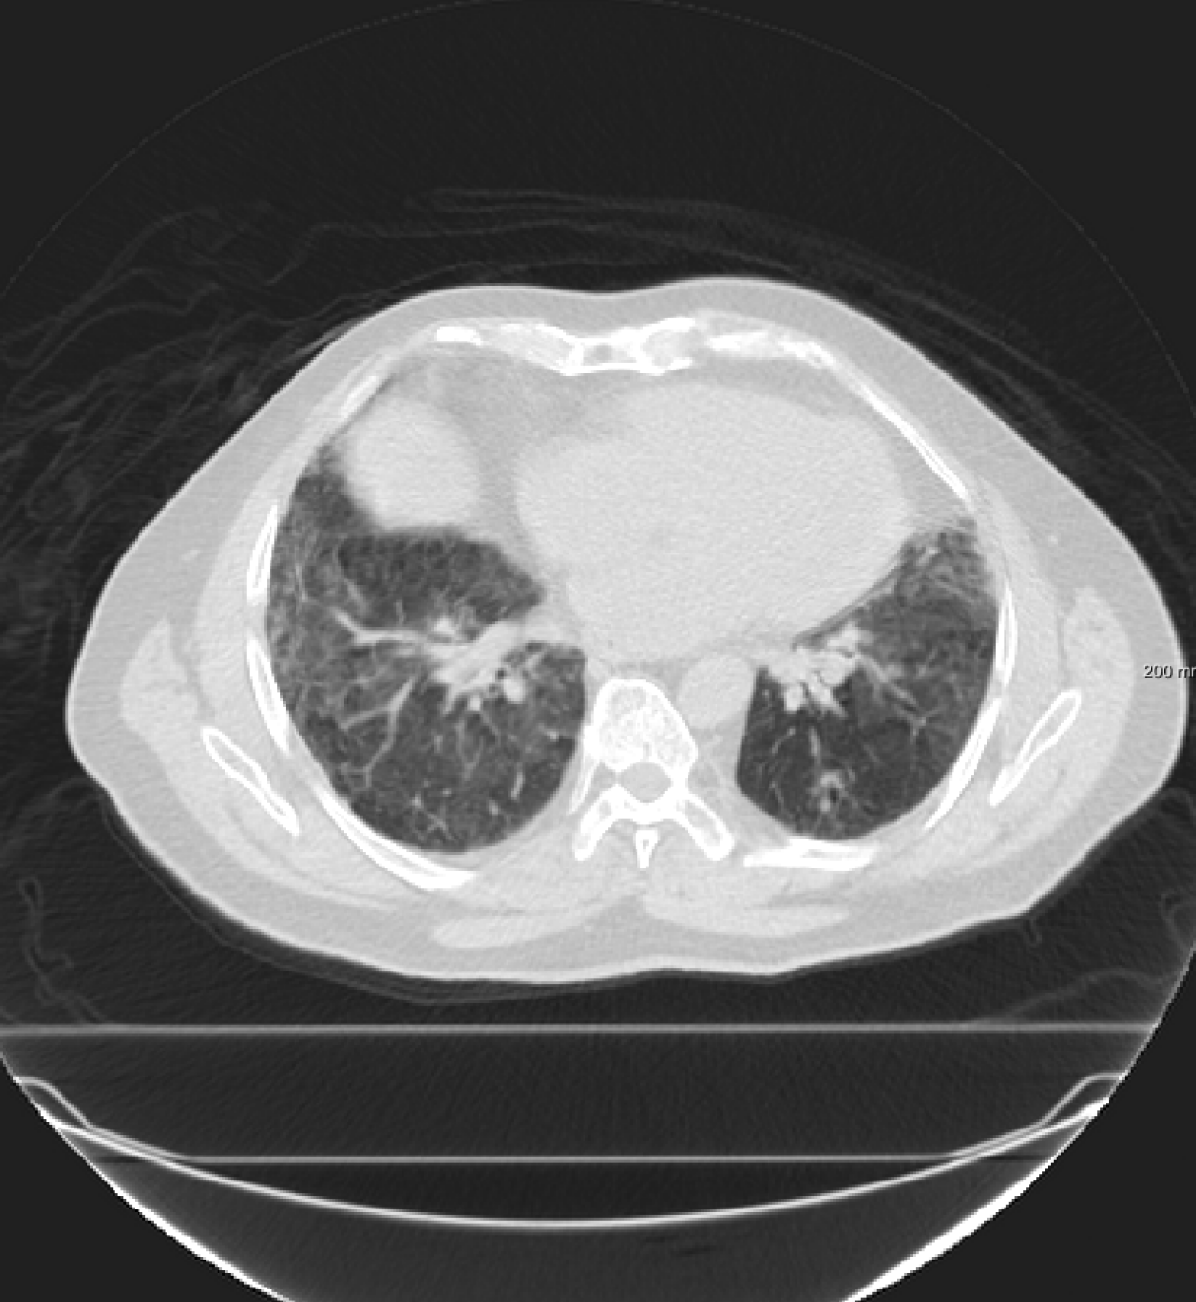

For the DIR-Lab-4DCT database, a comparison between RegNet and affine, B-spline (three resolutions), an advanced conventional registration method using sliding motion (Berendsen et al., 2014) and three other CNN-based methods (Eppenhof and Pluim, 2018; de Vos et al., 2019; Sentker et al., 2018) is available in Table IV. It can be seen that training with “S+M” improved performance slightly with respect to just “S”. Adding the respiratory motion category improved performance substantially, as these are inhale-exhale pairs; this is predominantly caused by the patients where the TRE after affine registration was still quite large. An example visualization is also available in Fig. 5(f), showing that adding the respiratory motion category can align images better in the diaphragm region. The advanced conventional registration method that leverages sliding motion (Berendsen et al., 2014) is still better than RegNet. Note that RegNet was not trained on the DIR-Lab-4DCT data, similar to Eppenhof and Pluim (2018); Sentker et al. (2018). However, de Vos et al. (2019) and Eppenhof and Pluim (2018)-DIR methods were trained on the same database but using cross-validation to report the results. Also note that the results reported in Sentker et al. (2018) are averaged over all phases of DIR-Lab-4DCT (T00 to T10), while the results of other CNN methods (including RegNet) are reported between the maximum inhale and maximum exhale phase (T00 and T50). These reported results are therefore likely somewhat better than the results for T00 and T50 only.